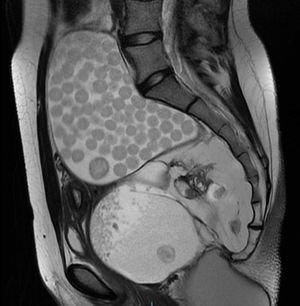

Paciente mujer de 23 años de edad, sin antecedentes conocidos, que consulta por retención aguda de orina recidivante. Se inicia estudio con ecografía abdominal, que se completa con TAC y RMN (figs. 1 y 2) de pelvis. Con hallazgos de teratoma sacrococcígeo de 12cm.

El teratoma quístico maduro es el tumor ovárico más común. Ofrece una imagen típica en RMN llamada en «bolsa de canicas», donde los glóbulos flotantes suelen tener un nido compuesto por detritos, material descamativo o vellos finos que es hiperintenso en T2 e hipointenso en T1.